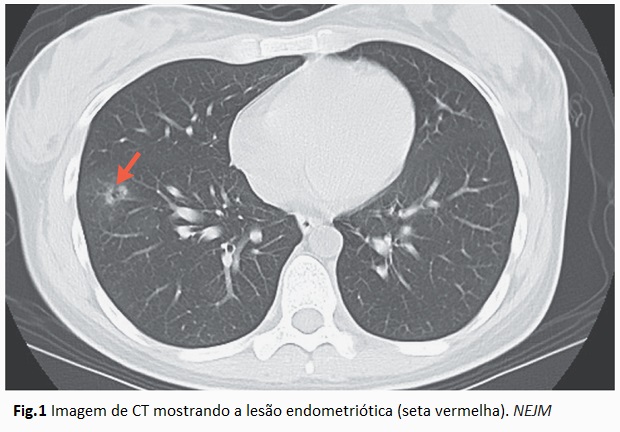

Uma mulher de 26 anos de idade apresentou-se ao hospital com hemoptise recorrente coincidindo com a menstruação. Hemoptise é a expectoração sanguínea ou sanguinolenta proveniente das vias aéreas inferiores (pulmões ou brônquios), geralmente caracterizada por tosse com sangue. Ela não tinha outros sintomas abdominais ou pélvicos. Tomografia computadorizada (CT) sem contraste do tórax da paciente revelou um nódulo cavitário com uma aparência fosca no lobo inferior direito do pulmão, e com dimensão de 11 mm (Fig.1). Uma resseção toracoscópica assistida por vídeo foi realizada. Análise histopatológica mostrou glândulas endometrióticas e estroma, confirmando o diagnóstico de endometriose torácica. Após intervenção cirúrgica, a paciente ficou livre de sintomas nos próximos 2 anos de acompanhamento. O caso foi descrito e reportado no periódico The New England Journal of Medicine (Ref.1).